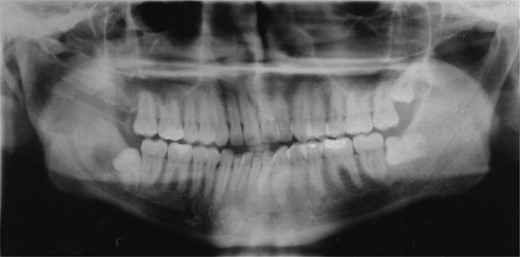

Plain films along with CT scan, with 3 mm slices, were performed a further year later and showed good bone regeneration in the right ramus and condylar neck (Figs 4 and 5). No evidence of cystic recurrence was seen and no abnormalities within the adjacent soft tissues. High-resolution magnetic resonance imaging also confirmed the absence of cystic remnants. The patient has now been reviewed for 5 years and there is no evidence of recurrence.